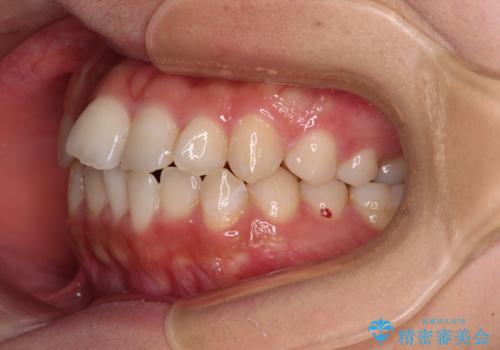

- 前歯のデコボコを気にして来院された患者様です。

当初予定通り、1年で治療を終えることができました。

後戻り防止はマウスピースで行うため、急に自己管理が必要となるため、移動の最後をマウスピース矯正で行うことで、マウスピース非装着による後戻りリスクを回避する工夫をしています。